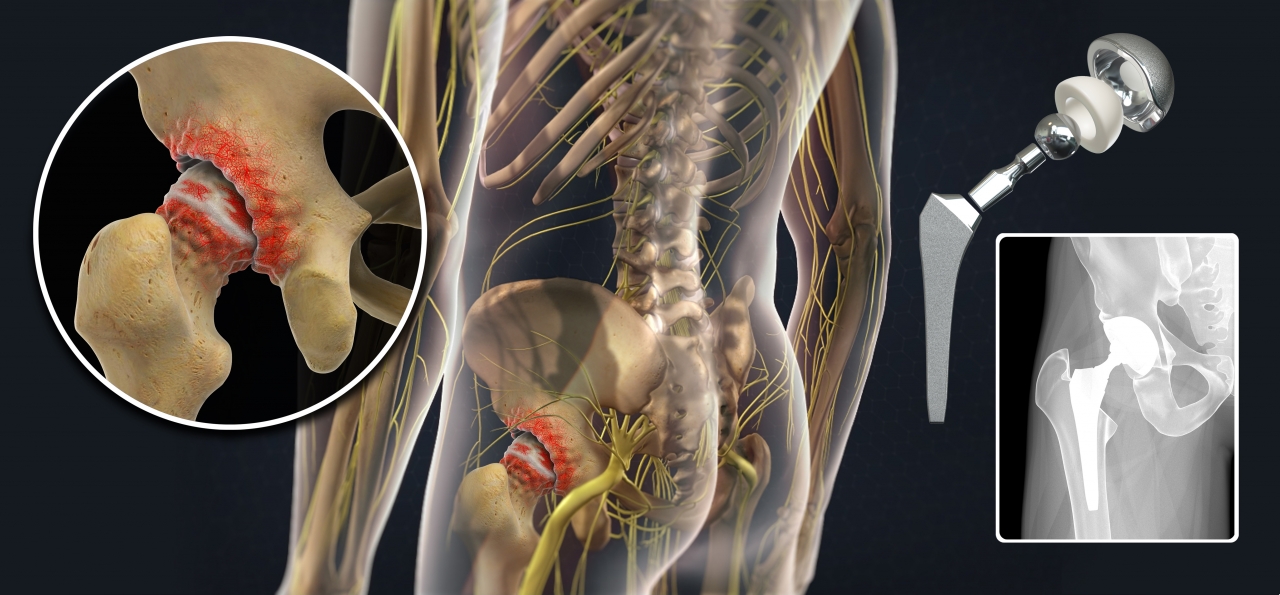

Эндопротезирование тазобедренного сустава: фото и схемы

:max_bytes(150000):strip_icc()/x-ray-illustration-of-hip-replacement-1254389829-281a949198324333972a407cc2e90760.jpg)